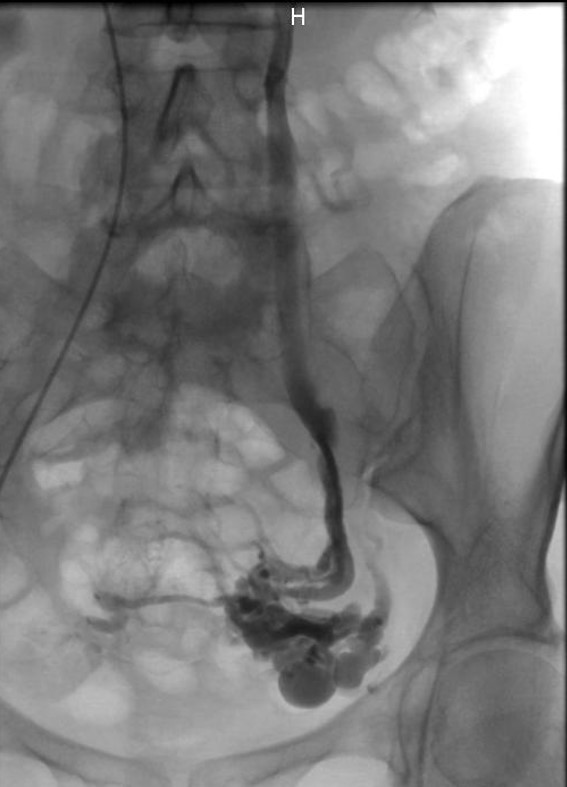

Cette intervention est réalisée par un radiologue interventionnel qui, après anesthésie locale et ponction de la veine fémorale (piqûre en haut de la cuisse au niveau du pli de l’aine), va y insérer un petit cathéter (tuyau) de quelques millimètres et cartographier l’ensemble du réseau veineux pathologique grâce à une injection de produit de contraste iodé (phlébographie). L’intervention est réalisée sous contrôle radiologique en temps réel.

Une fois le cathéter en place le radiologue injecte l’agent embolisant (colle biologique bio-résorbable) jusqu’à boucher les veines dilatées et le réseau variqueux ce qui redirige le flux sanguin vers le réseau veineux non pathologique faisant disparaitre les phénomènes de stase et de congestion veineuse.